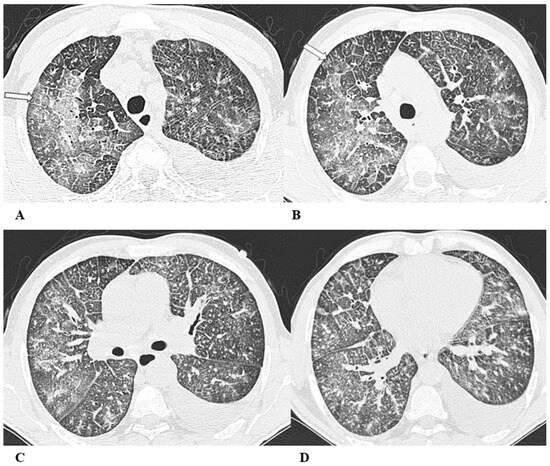

Figure 1.

Organizing pneumonia (OP). Organizing pneumonia is determined by the presence of granulation tissue buds in the alveoli, alveolar ducts and distal bronchioles. On HRCT, OP is characterized by diffuse and bilateral areas of consolidation and ground-glass opacities (GGOs), often migratory, with predominantly peripheral/subpleural and peribronchovascular distribution [9,12]. Other OP findings are the “reversed halo sign” (a focal area of GGO surrounded by a ring of denser air-space consolidation; if the surrounding ring is incomplete, it is mentioned as the “atoll sign” [16]) and, rarely, centrilobular nodules.

(A–D) A 64-year-old man with a diagnosis of small-cell lung cancer with adrenal and brain metastases, treated with nivolumab. Six months after beginning immunotherapy, the patient presented progressive dyspnea and dry cough. Chest auscultation revealed diffuse crackles associated with a moderately restrictive functional pattern. The blood count did not show significant leukocytosis but showed increased inflammatory indexes. The patient benefited from a temporary suspension of immunological therapy with steroid intake, but the subsequent relapse forced a radical change in therapeutic strategy.

Axial chest CT images (A–D) show bilateral confluent areas of GGOs and peripheral and peribronchovascular consolidative opacities.

The structural alteration of the right pulmonary hilum due to the presence of neoplastic tissue, with the infiltration of the ipsilateral main bronchus (A) and the “reversed halo sign” (white arrow (D)), are also visible.